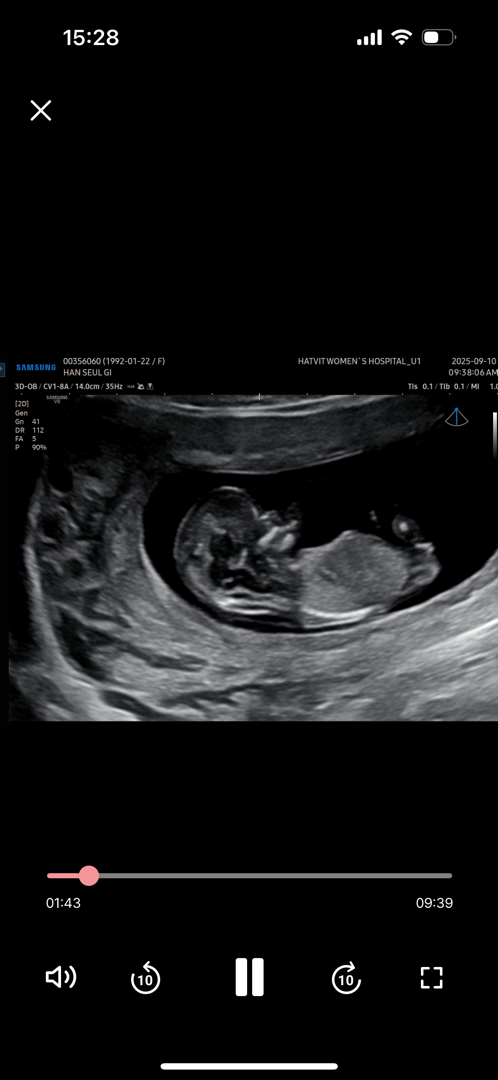

이걸로도 알수 있을까요.. 12주 1일이에요